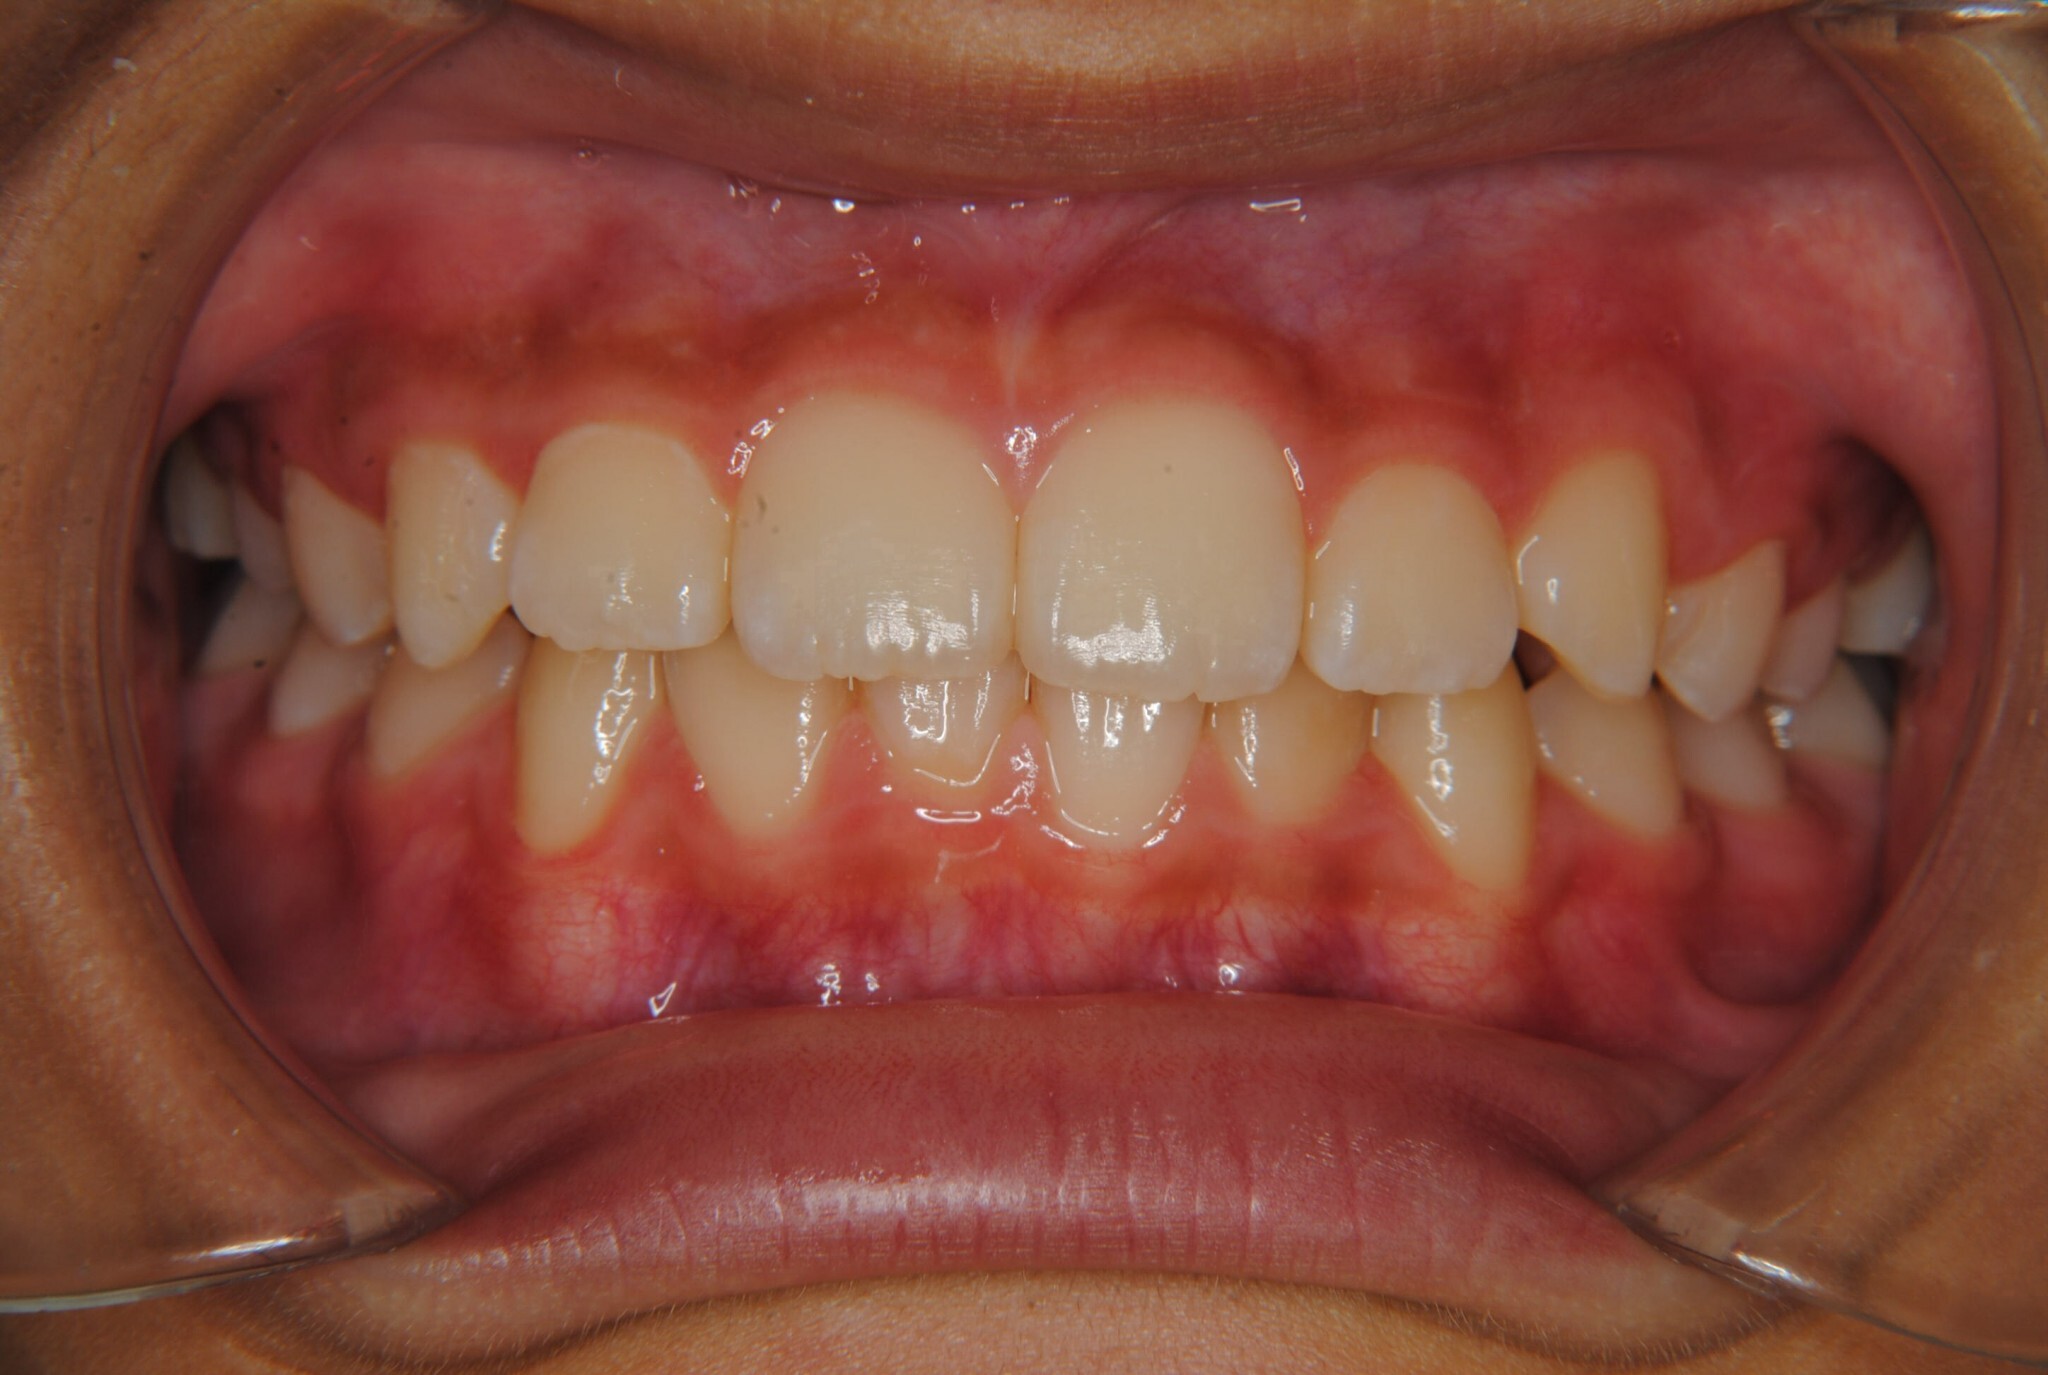

②診断名:Ⅰ級叢生

③年齢:初診時(左写真)8歳6か月、終了時(右写真)11歳4か月

⑧リスクと副作用:特に大きなリスクや副作用はありませんでした。拡大床装着直後は違和感があったようですが、特に痛みを感じることなく6.5mmまで拡大できました。その後永久歯への生え変わりも順調で、ほぼ正常な咬み合わせになりました。この後11歳4か月まで観察し、7番目の奥歯である12歳臼歯がきちんと咬んだので終了となりました。